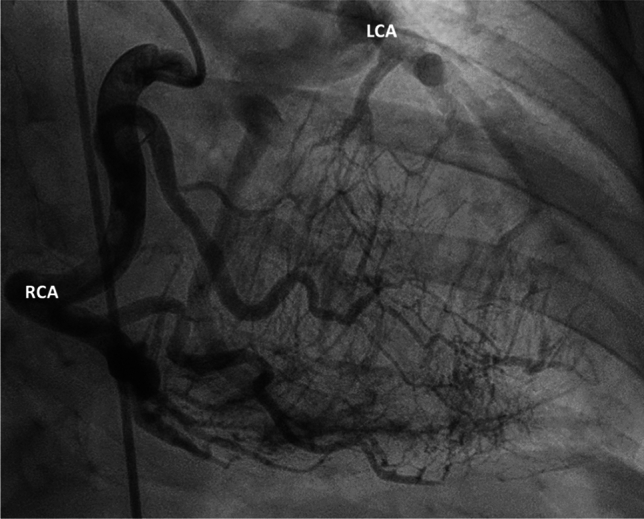

A 39-year-old women with newly diagnosed ALCAPA syndrome during pregnancy.